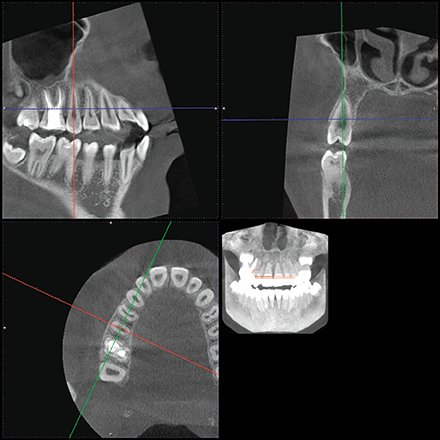

The location of the roots of the maxillary right dentition closely proximate the buccal and palatal cortical plates of the alveolar processes, which were thin particularly at the canine and first premolar with thicker cortex regions lateral to the second premolar and first molar (Figs. 4-7).

Fig. 7 Fig. 8